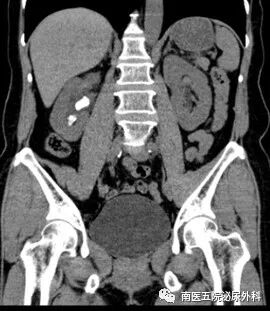

患者何某某,性别:女,年龄:57岁,入院时间:2023.8.17,患者主诉:右侧腰腹部疼痛伴肉眼血尿10天。诊断:右肾多发结石并右肾积液。术式:经尿道钬激光输尿管软镜碎石取石术。

术前影像检查

术后复查,结石已全部清除